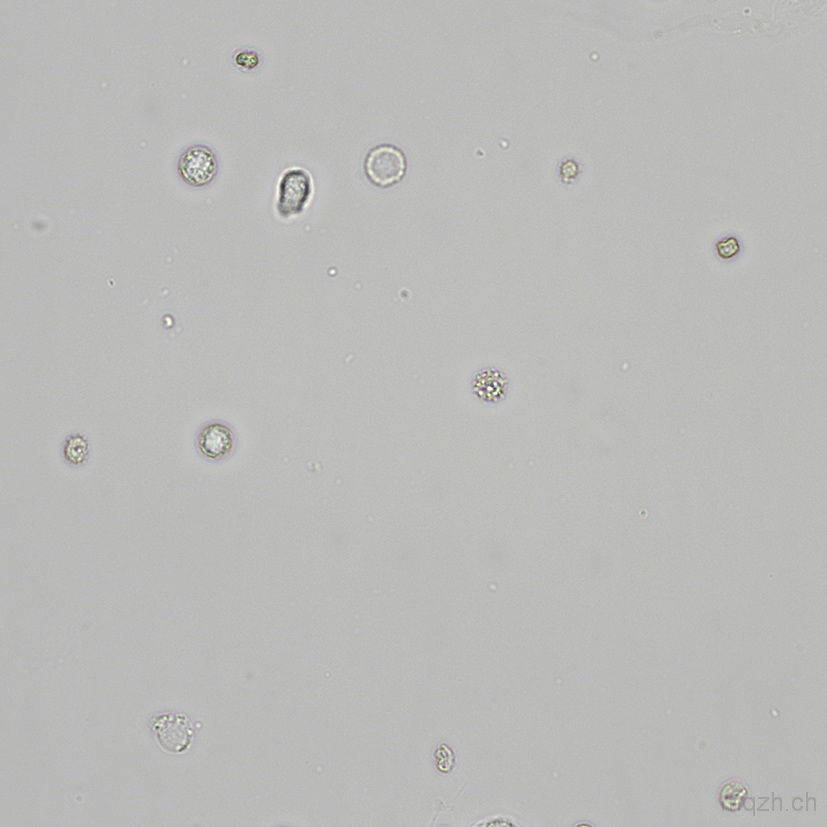

MQ 2025-4 Urinary Sediment U4